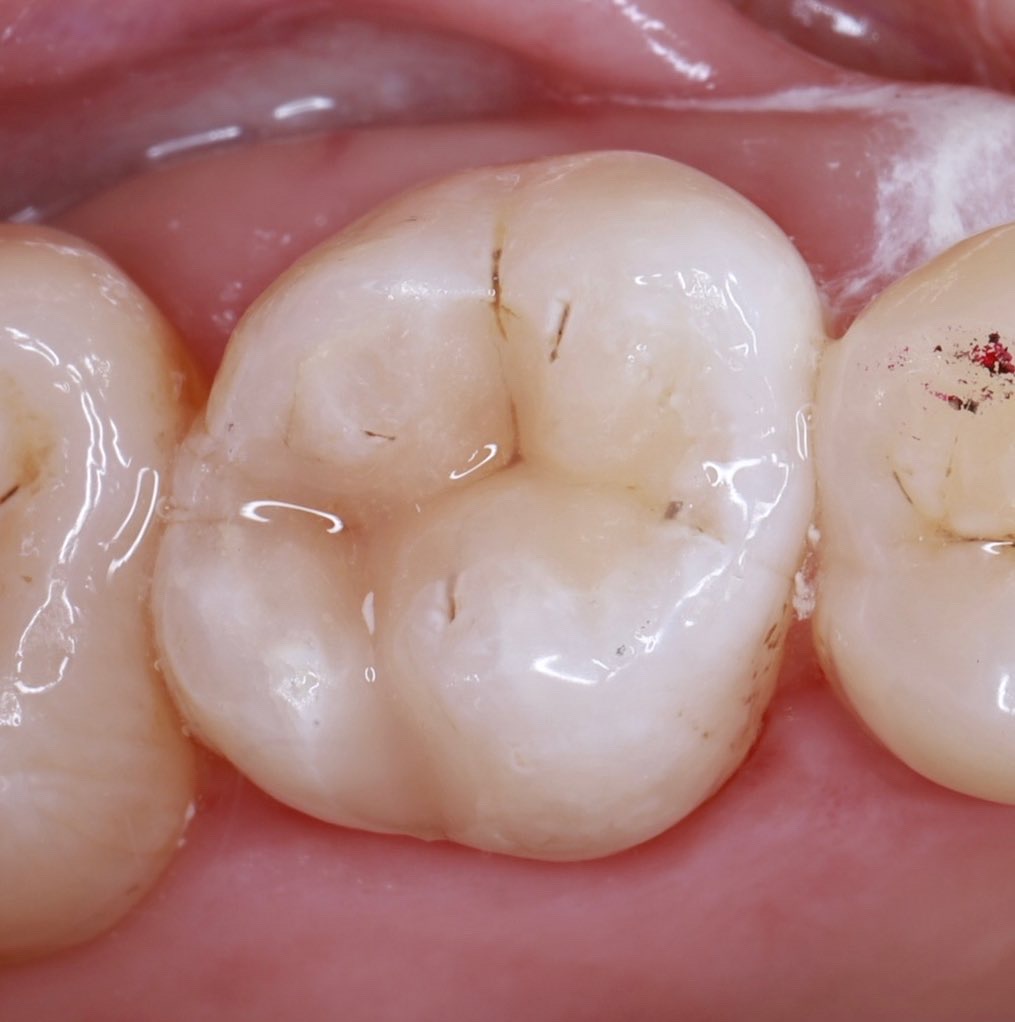

01精密根管治療

「抜くしかない」と言われた歯でも、根の中の感染を適切に抑えられる治療技術があれば、歯を残せる可能性があります。根管は非常に細く複雑で、わずかな取り残しが痛みや腫れの再発につながることもあるため、当院では必要に応じてCTやマイクロスコープを活用し、原因を見極めながら丁寧に処置を進めます。

大杉歯科医院が大切にしているのは、早く終える治療ではなく、歯を守る治療。津市で、できるだけ天然歯を残したい方の選択肢になれるよう取り組んでいます。症例1

- 治療名

- マイクロスコープとラバーダムを使用した精密根管治療

- 患者様

- 30代男性

- 執刀医

- Dr. 大杉

- 治療期間

- 3ヶ月

- 治療費

- 精密根管治療:130,000円(税込)

築造:40,000円(税込) - リスク

- 治療中〜治療後に痛みが出る場合あり

再感染・治癒不全の可能性

補綴後も定期管理が必要